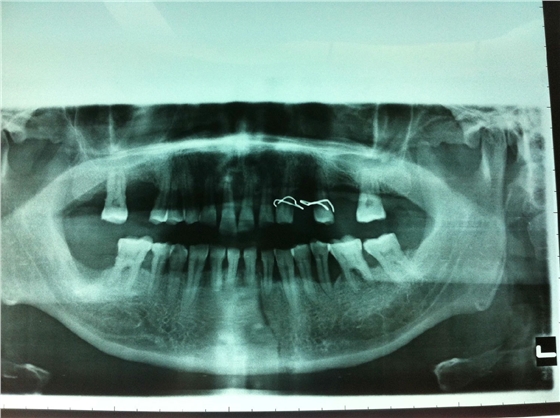

患者男性,主因左面部反復(fù)腫脹半年余,就診后行全景片檢查,發(fā)現(xiàn)下頜骨多發(fā)性囊腫,初步診斷為多發(fā)性頜骨囊腫綜合征,安排住院手術(shù)。

入院后全麻下手術(shù)治療,左側(cè)下頜骨囊腫較大,術(shù)前考慮病理性骨折可能,準(zhǔn)備鈦釘鈦板固定,術(shù)中摘除囊腫后,發(fā)現(xiàn)下頜骨下緣骨量尚可,未給予固定。術(shù)后病理診斷為下頜骨角化囊腫,考慮到患者可能為基底細(xì)胞癌綜合征,術(shù)中切除頸部皮膚痣兩處,術(shù)后病理診斷為:皮膚痣,排除基底細(xì)胞癌綜合征?;颊哂凶髠?cè)第六肋骨分叉肋,綜合以上特征,最終診斷為多發(fā)性頜骨囊腫綜合征。